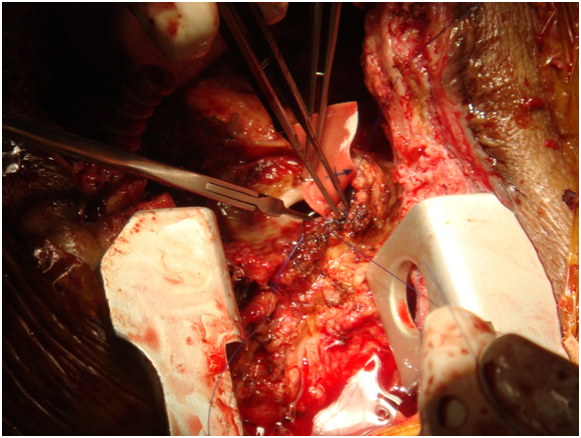

Chest incision was very technical-started from below with oscillator saw upto upper 1/3rd of sternum near aneurysm. Now upper part from above-near aneurysm curved the saw to right avoiding the aneurysm, put small retractor now gradually cut through bony surface so not went into graft and go around aneurysm without rupturing it but suddenly aneurysn came to leak--now no way--gentle pressure on leak and proceeded for total circulatory arrest. During going to total circulatory arrest, dissection around heart was done through diaphragmatic surface and right side. Now at 180C total circulatory arrest was done, taken out graft, found oval shaped opening at ascending aorta, a Dacron patch taken and covered it by continuous proline suture.

Figure 5: Huge clot inside.

Figure 6: Under Total Circulatory Arrest proximal part of aorto axillary graft removed.

Figure 7: Oval shaped opening is found in aorta.